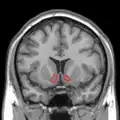

Dopamine and serotonin- MRI coronal slice showing nucleus accumbens outlined in red